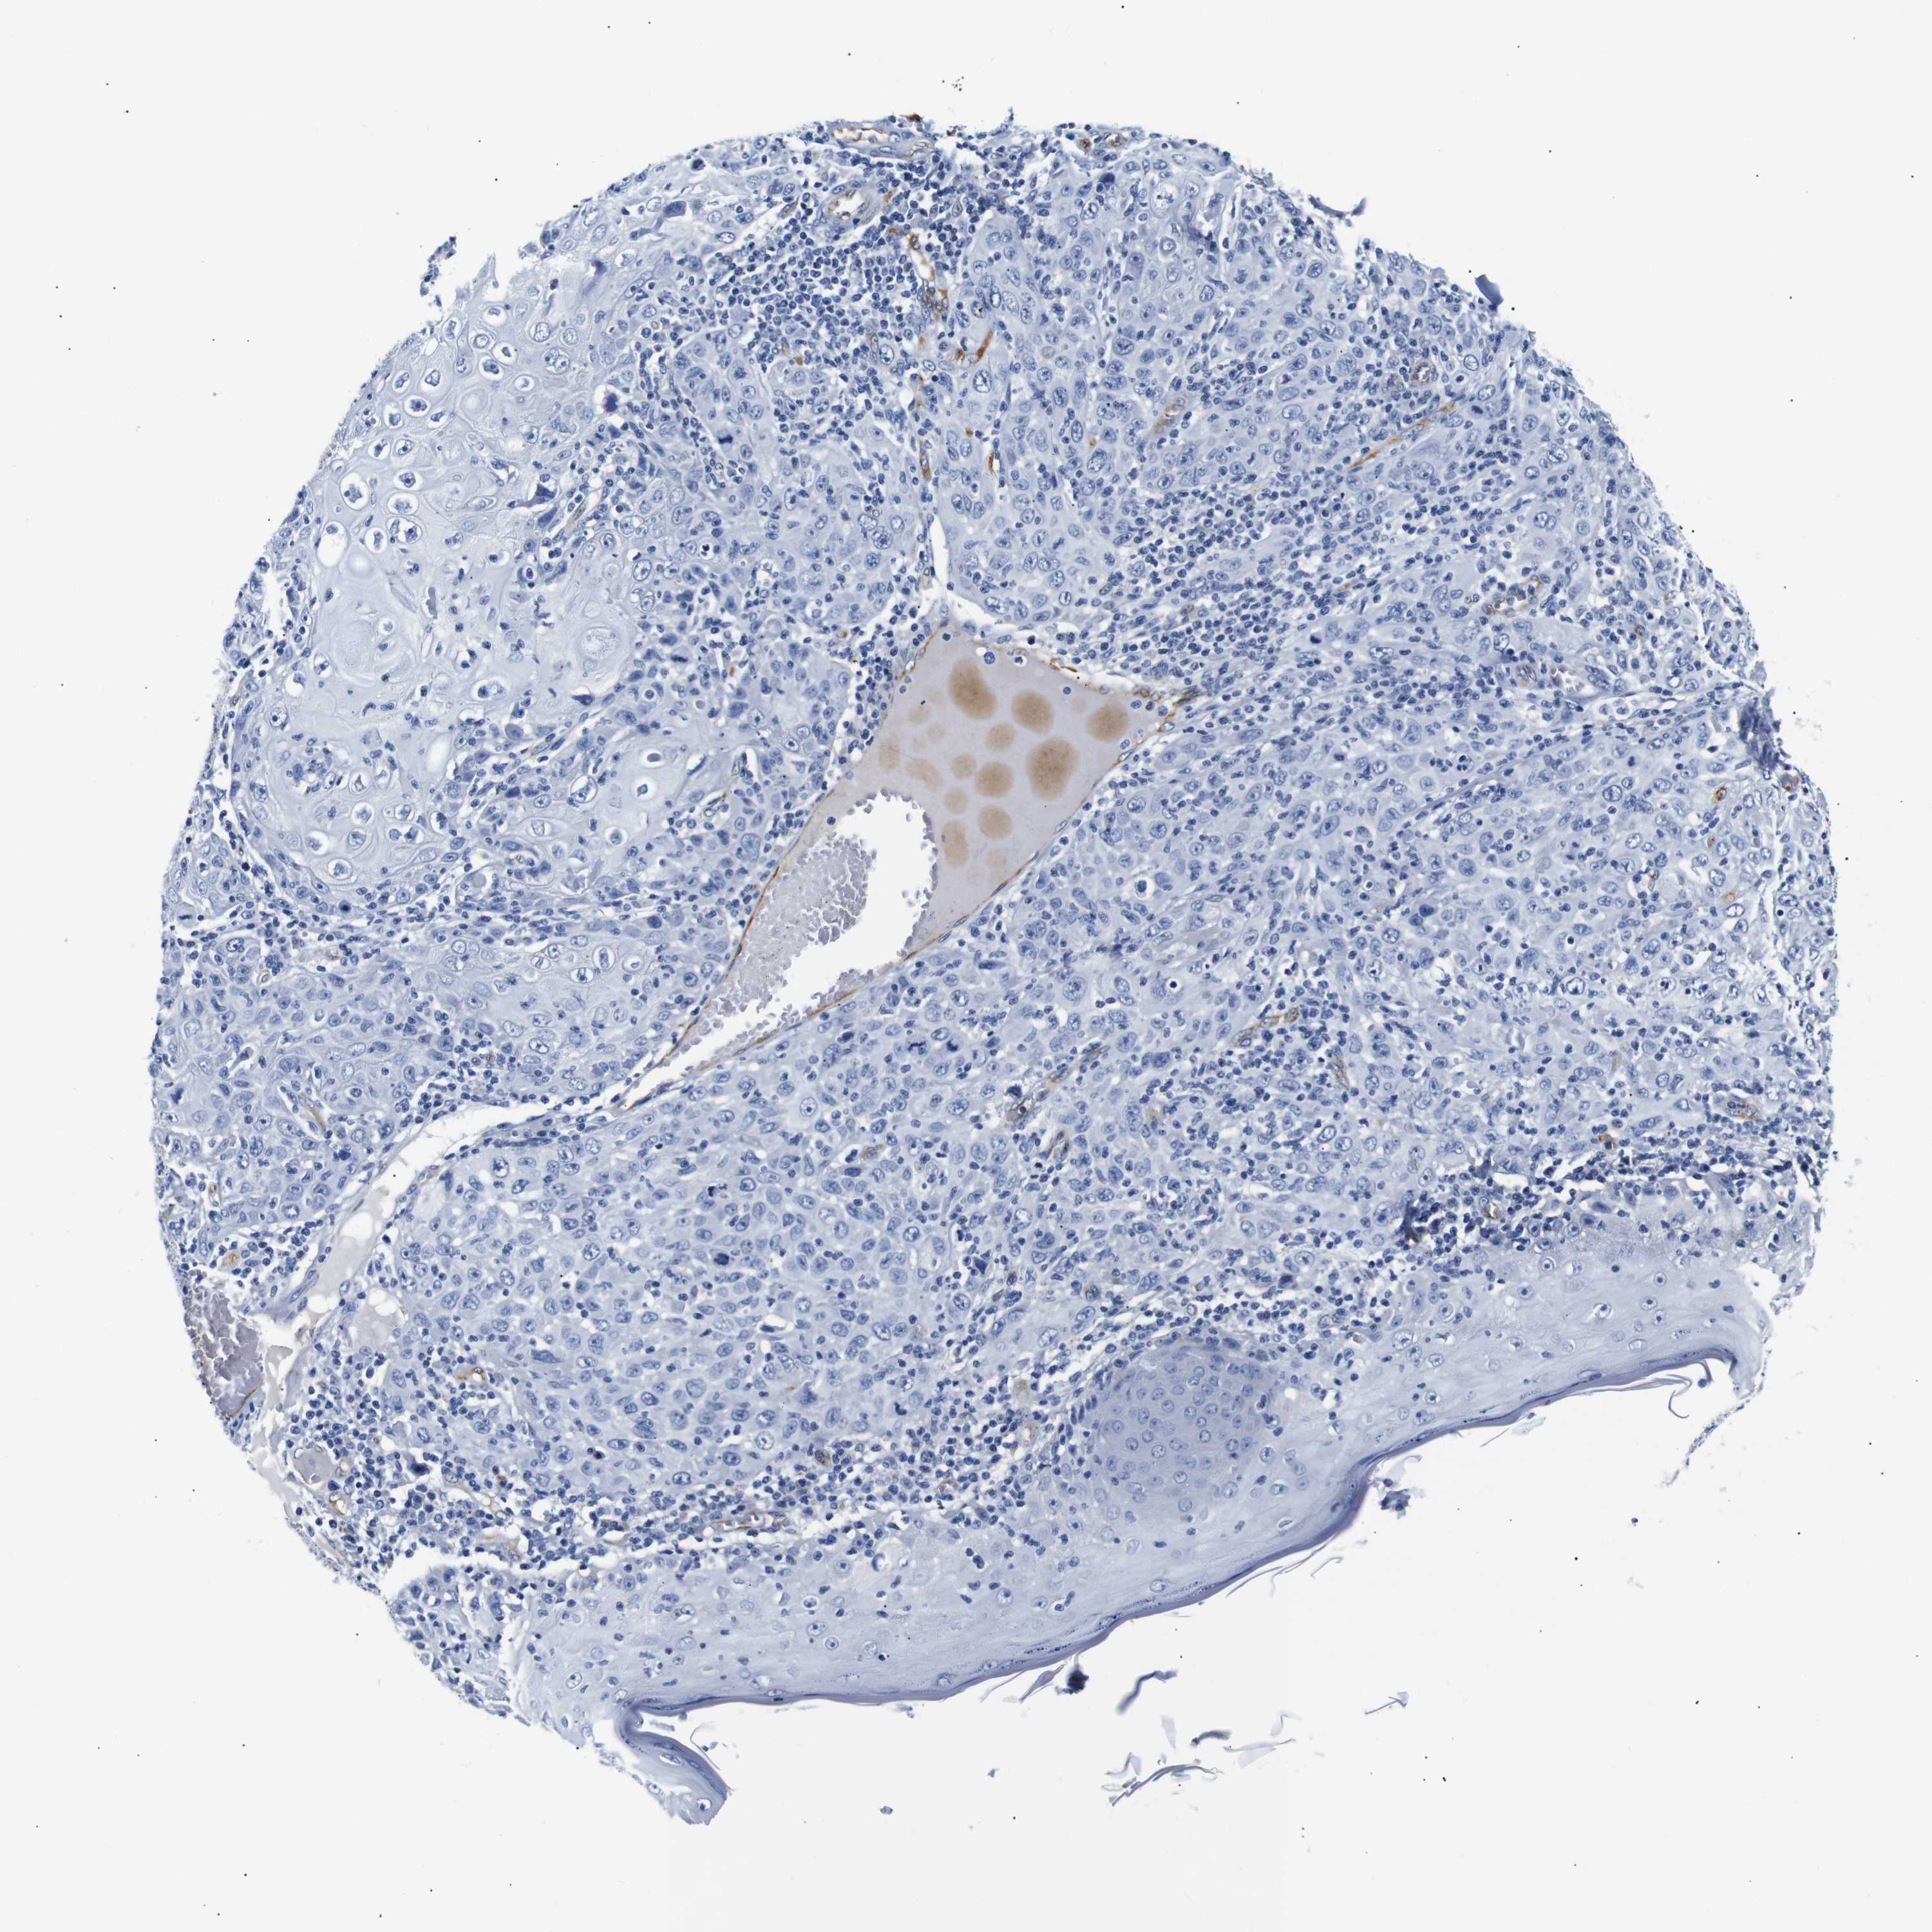

SKIN CANCER - Protein expressioni

A mouse-over function shows sample information and annotation data. Click on an image to view it in a full screen mode. Samples can be filtered based on level of antibody staining by selecting one or several of the following categories: high, medium, low and not detected. The assay and annotation is described here.

Antibody stainingi

Antibody staining in the annotated cell types in the current human tissue is reported as not detected, low, medium, or high, based on conventional immunohistochemistry profiling in selected tissues. This score is based on the combination of the staining intensity and fraction of stained cells.

Each image is clickable and will lead to virtual microscopy that enables deeper exploration of all samples and also displays staining intensity scores, fraction scores and subcellular localization as well as patient and tissue information for each sample.

Antibody HPA005895

Antibody CAB013536

Squamous cell carcinoma, NOS

Basal cell carcinoma